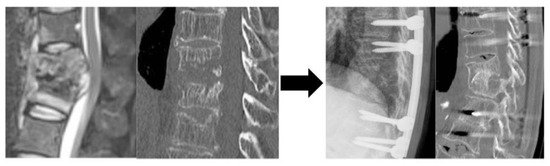

Figure 3.

Representative case of Group C with planned ASF plus posterior instrumentation A Preoperative CT: Bone destruction at the T11 and T12 vertebrae. B Immediate postoperative X-ray: Trans-extrapleural anterior scraping and iliac bone grafting with simultaneous posterior instrumentation. C Postoperative CT: Bone fusing was achieved at 1 year postoperatively. Abbreviation: CT, computed tomography; T, thoracic; ASF, anterior spinal fusion.